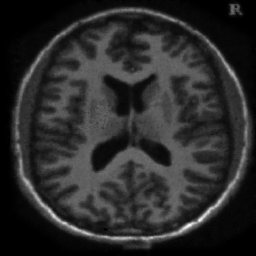

4.1. Uniform Gaussian noise

In this first experiment, we consider the denoising problem with brain scan images. The first set consists of images of pixels and Gaussian noise with zero mean and variance . The original and noisy images are shown in Figure 4.1. The domain decomposition-semismooth Newton algorithms run with the parameter values , , and . The results are shown in Figure 4.2. From the surface representation of , we can observe that is continuous and its shape is related to the one of the original image. In particular, the regularization is stronger in homogeneous regions in the image, and weaker where the image intensity undergoes variations on a smaller scale.

In Table 4.1 the performance of the different methods is compared. For all of them, only the first 2 domain decomposition iterations were considered. The total number of SSN iterations differ at most by one. The impact of the domain decomposition method becomes clear when comparing the computing times of the methods, corresponding to one, two and four subdomains. The computing time is significantly reduced. The effect of the optimized transmission conditions can be realized when comparing the gap between subdomains, which is much lower in the case of optimized transmission conditions () than in the standard Schwarz method ().